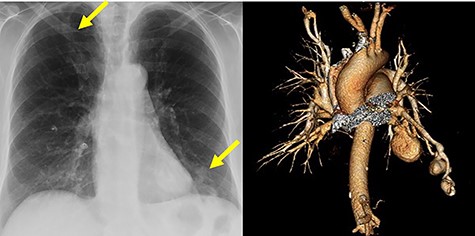

A 76-year-old woman presented to the emergency department (ED) at a tertiary care hospital complaining of worsening left-sided chest and shoulder pain. The patient underwent diagnostic imaging during her workup in the ED, which included a computed tomography scan of the chest. This revealed three sequential PAVMs off the inferior lingual artery subsegmental branches. The largest had aneurysmal dilation of 3.4 cm, whereas the others measured 2.2 and 1.3 cm in diameter. Additionally, a PAVM in the right upper lobe had aneurysmal dilation of 1.2 cm. All had arterial supply with diameter measuring >3 mm (Fig. 1). Interestingly, the patient had an accessory fissure between the superior and inferior segments of the lingual. No cerebral or gastrointestinal tract arteriovenous malformations were found in workup.

Chest radiograph and computed tomography volume rendered images of multiple aneurysmal PAVMs, including three in lingula and one in right upper lobe. Yellow arrows denote aneurysms.